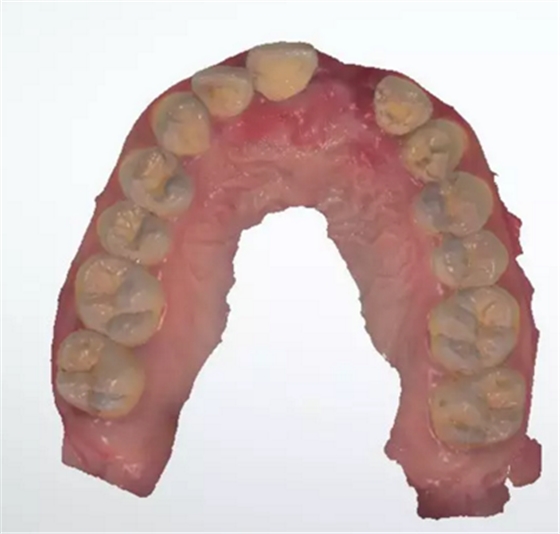

術(shù)前檢查

1.術(shù)前CT

2.術(shù)前植體設(shè)計(jì)

3.術(shù)前導(dǎo)板設(shè)計(jì)